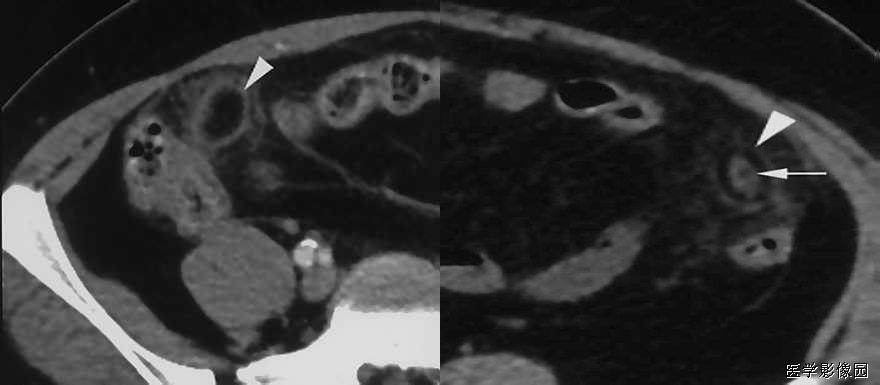

10、 箭头征

“箭头”征阑尾炎的一个比较典型的CT表现,是造影剂汇集在盲肠尖端(阑尾起始部)形成的箭头样、鸟嘴样改变,是阑尾炎症蔓延到盲肠尖肠壁的结果。如果在盲肠的尖端汇集的不是高密度的造影剂而是气体,那么显示的就是空箭头征。如果造影剂汇集于结肠憩室的口部,也会显示这样的征象。箭头征也见于急性阑尾炎的CT增强扫描中,急性阑尾炎患者的阑尾血流比率比正常肠道高,增强扫描时可见其强化。部分患者由于炎症时肠壁血管内血栓形成,使局部血流受阻,阑尾血流比率可等于或低于正常肠道,甚至无血流灌注,CT上阑尾表现为等密度,低强化或无强化;另外阑尾炎时,其邻近肠管可继发炎症,局部血流增加,有时CT上可见局部盲肠壁增粗, 强化时增强, 似箭头一样指向病变阑尾。“箭头”征是造影剂汇集在盲肠尖端(阑尾起始部)形成的箭头样、鸟嘴样改变,是阑尾炎症蔓延到盲肠肠壁的结果。见到此征象, 有文献报道,阑尾炎的特异度几达100%。有些患者由于炎症较轻,肠道血流可无明显改变;也有些病例,可能是肠壁部分血流受阻,与炎症引起的血管扩张相抵消。因而其血运明显受阻,局部造影剂减少所致。

阑尾粪石可能增强阑尾穿孔的机会,当发现阑尾钙化或阑尾粪石,同时合并阑尾周围炎时,是诊断阑尾炎的可靠征象。阑尾粪石也可出现在阑尾穿孔形成的脓肿或蜂窝织炎内。

阑尾周围炎表现为阑尾周围脂肪组织中条索状、斑片状密度增高影(称脂肪条带征)、结肠后筋膜增厚、阑尾周围液体渗出,局部形成脓肿。阑尾周围炎只是阑尾炎的一种主要间接征象,不能单凭此诊断阑尾炎。阑尾周围炎性反应或右下腹脓肿提示阑尾炎,但Crohn 病、盲肠炎、憩室炎、肿瘤穿孔和盆腔炎等亦可有相似的表现,应与之鉴别。

阑尾增粗,壁增厚、阑尾腔内可减低密度条带影,为阑尾腔内的液体,阑尾根部与盲肠交界处的官腔内进入造影剂形成边缘不规则的尖角状,即“箭头征”